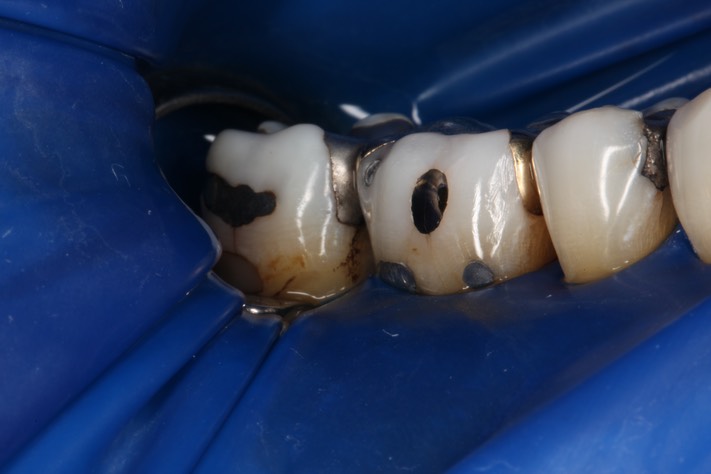

Dr. May Chang’s cases

March 1, 2012

February 2, 2012

January 5, 2012

Hilo November 4 and December 3, 2011

Mark Chun #30 finish